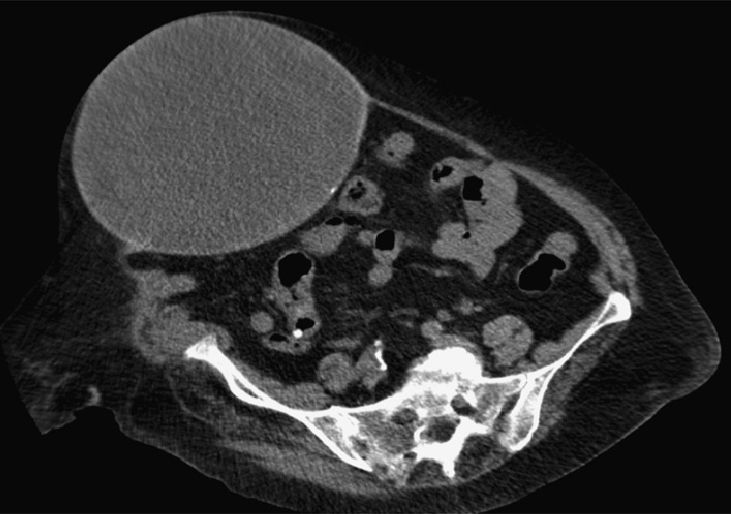

A 79-year-old woman was referred to our department due to an abdominal wall tumor (Fig. 1). Her medical history included midline laparotomy in 1982 and strangulated incisional hernia repair (with polytetrafluoroethylene prosthesis) in 2006. Computed tomography showed a cyst measuring 31cm×19cm×17cm on the right rectus abdominis muscle (Figs. 2 and 3). The lesion was completely resected, with primary closure of the defect and placement of polypropylene mesh. The pathology study showed evidence of granulation tissue with chronic inflammation (anterior wall), granulomatous reaction to a foreign body, fibrosis (posterior wall) and no malignancy. Pseudocyst is defined as a collection of fluid that is not covered by epithelium. There have been other denominations such as chronic seroma cyst and giant fibrous cyst, but the histology confirms the pseudocyst.

Fig. 2